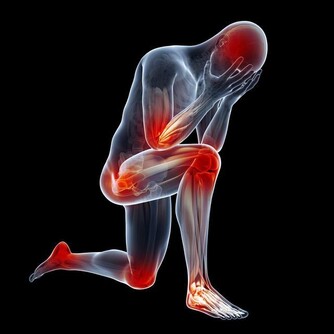

運動少,血管垃圾多正常人皮膚上每平方毫米約有600根毛細血管,平時只開放100—200根,多運動能讓更多的毛細血管開放,促進血液微循環;而長期不運動,血管內的垃圾會逐漸累積,形成粥樣硬化斑塊這個“不定時炸彈”,還會影響到毛細血管供血,並且隨時可能被引爆。

堅持適度的體育鍛煉,不但可增加脂肪消耗,減少體內膽固醇沉積,降低血脂,加速血液循環,防止血液瘀滯,對於血管的健康很有好處。研究顯示,每天運動半小時,如騎自行車、游泳、乒乓球、慢跑、慢跑、散步、柔軟體操、打太極拳、爬樓或登山,都能起到減肥消脂的作用,提高血管“年輕化”程度,防止變老。